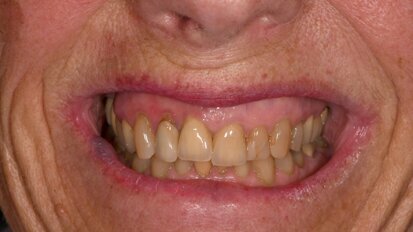

Anterior crowns on teeth and an implant

Dental technicians have so many different restorative materials and design and finishing concepts available to them that it can seem difficult to select the...